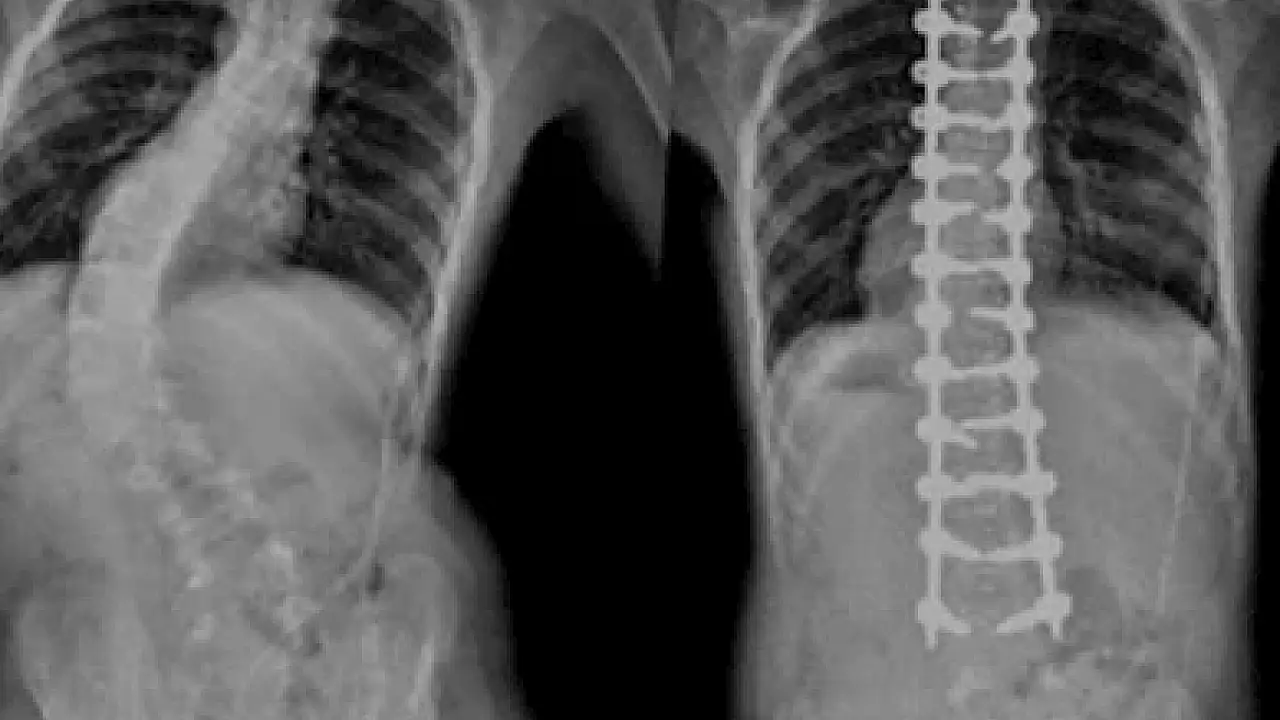

Doğru tanı için omurganın tamamına röntgen çekilmesi gerektiğine dikkat çeken Doç. Dr. Çaçan, “Genellikle göğüste asimetri oluşur, arka taraftan omurgaya bakıldığında bir omuz diğerine kıyasla daha düşük durur. Bir taraftaki kürek kemiği daha belirgindir ve bel kuşağında asimetri görülür. Sırttaki asimetri kişi öne eğildiğinde daha da belirginleşir ve eğriliğin büyüklüğü röntgen üzerinde yapılan ölçümlerle belirlenir. Ölçümlere göre skolyozun hangi tip olduğu anlaşılarak tanı konulur. Hastanın ergenlikten sonra iskelet sisteminin olgunlaşmasıyla birlikte ilerlemesi durur” ifadelerini kullandı.

Doç. Dr. Mehmet Akif Çaçan, skolyoz tedavisinin kişiye özel planlandığını ifade ederek şu bilgileri verdi: "Skolyoz tedavisi eğriliğin tipine, büyüklüğüne ve hastanın yaşına göre değişkenlik gösterir. Günümüzde skolyoz tedavisinde cerrahi dışı ve cerrahi yöntemler kullanılır. Cerrahi olmayan yöntemler daha çok eğrilik miktarı az olan hastalarda eğriliğin ilerlemesini yavaşlatmak amacıyla kullanılır. Bunlar arasında en önemlileri korse ve egzersizdir. En sık görülen idiopatik skolyozda 20 derecenin altındaki eğrilikler çoğu zaman sadece takip edilir. Daha büyük ve ilerleme riski olan eğriliklerde korse kullanılır. 40 derecenin üzerindeki eğrilikler genellikle cerrahi ile tedavi edilir. Konjenital yani doğuştan oluşan skolyozda çoğu zaman cerrahi tedavi gerekir. Cerrahide de füzyonlu ya da füzyonsuz yöntemler mevcut olup bunlar da hastanın ihtiyacına göre uygulanır."